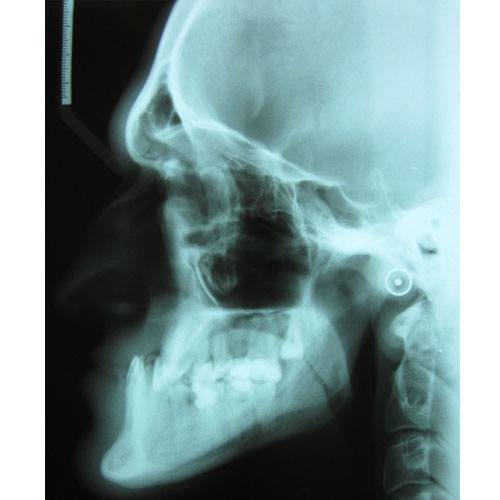

Leczenie ortodontyczne może być rozpoczęte w każdym wieku. Niektóre wady wymagają jednak leczenia kompleksowego, wielospecjalistycznego. Skojarzone leczenie dotyczy wad ortognatycznych, czyli wynikających z nieproporcjonalnej budowy szkieletu. Przykładem takiego leczenia jest leczenie progenii.

Nasze rezultaty